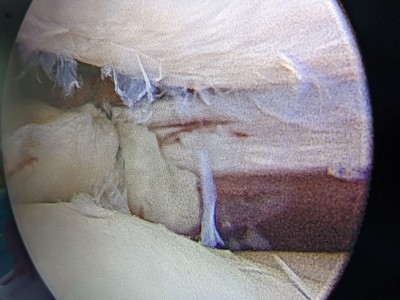

“Pacientul a suferit leziune gravă de menisc extern subluxantă, în langhetă, de corn posterior în totalitate și clivaj orizontal al părții medii meniscale externe. Am efectuat sutura de menisc extern, corn posterior, cu 2 ancore (prin tehnică în lasou) și partea medială, pentru ruptura veche în toartă de coș, ruptă după al doilea traumatism.

Procedura intervențională a fost minim-invazivă (laparoscopică), tehnica de sutură în lasou fiind ceea mai nouă și mai fiabilă (AOSS USA).